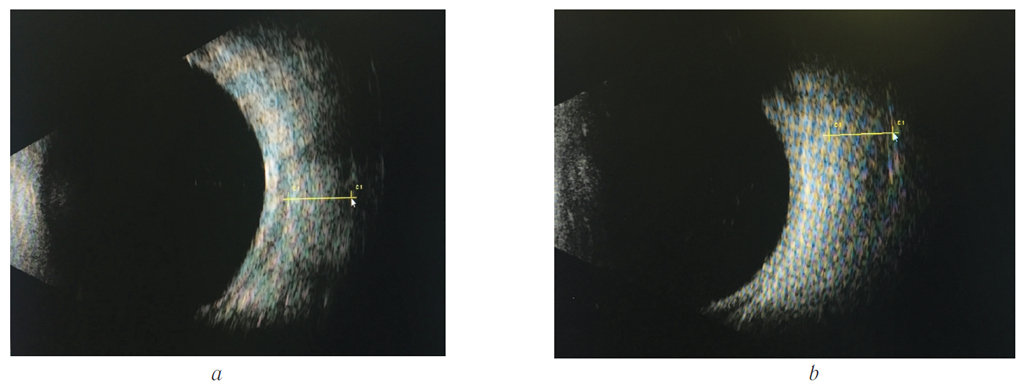

Эхография орбит: нижняя и внутренняя прямая мышцы резко увеличены в размерах (рис. 2).

Рис. 2. Эхограммы орбит того же больного: a — нижняя прямая мышца, 6,5 мм; b — внутренняя прямая мышца, 6,2 мм

Fig. 2. Echograms of patient’s orbits: a — lower rectus, 6.5 mm; b — internal rectus, 6.2 mm